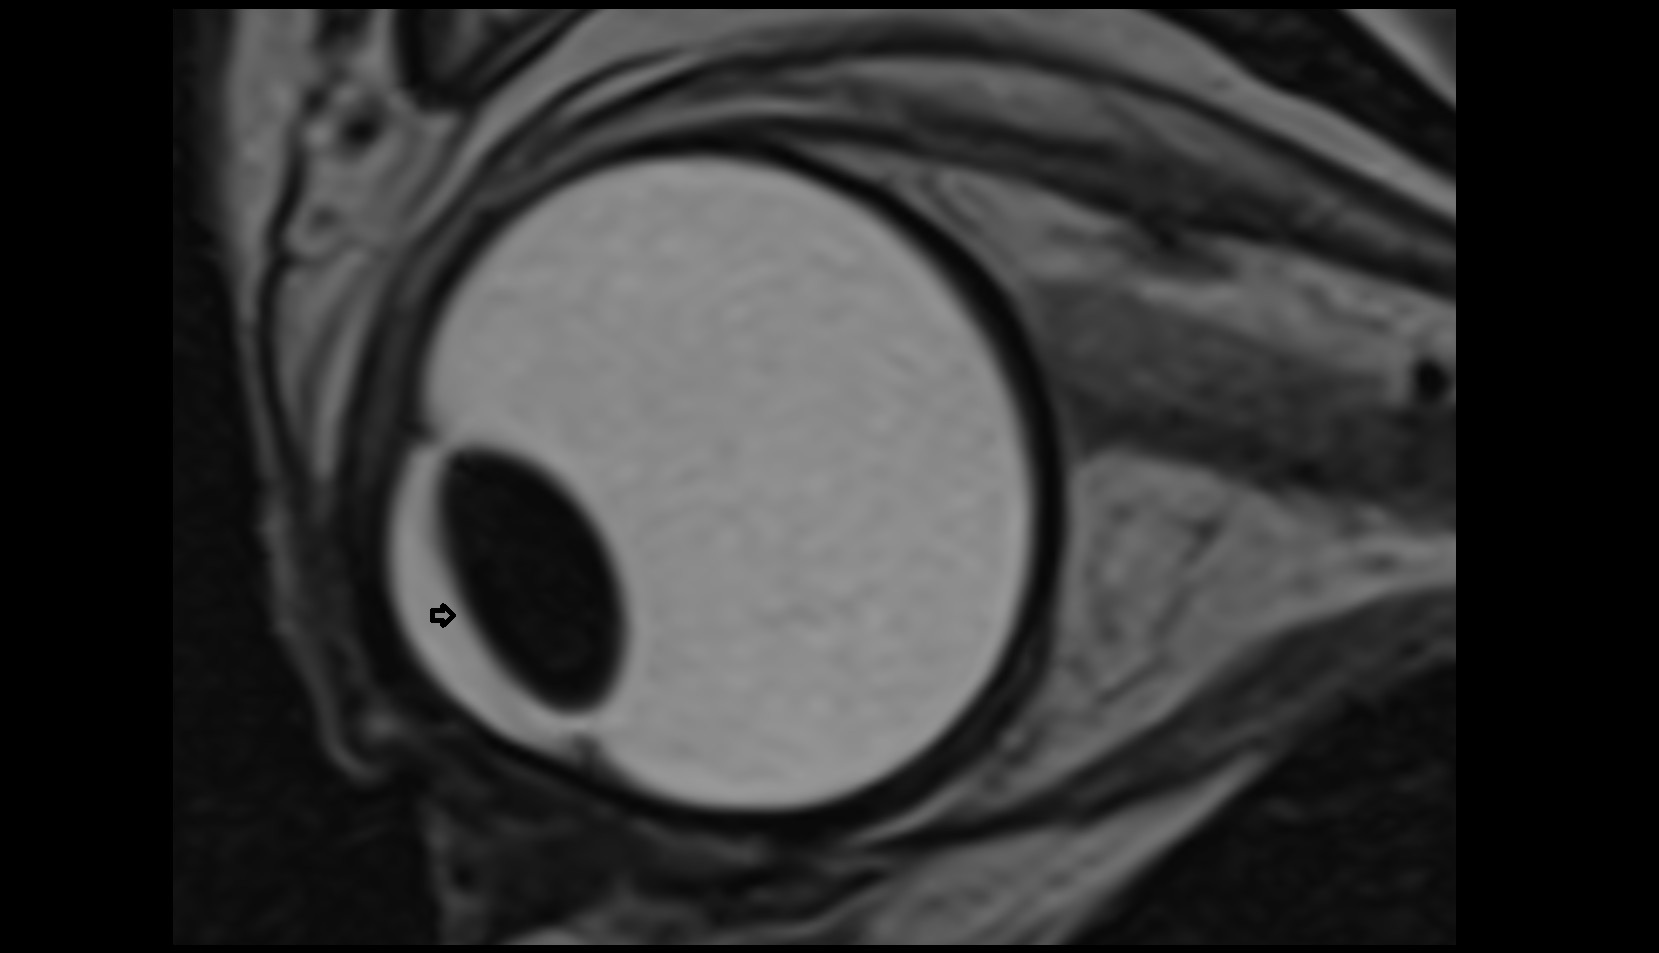

- Peripheral zone of prostate

- Anterior Fibromuscular Stroma of prostate

- Central zone of prostate

- Transitional zone of prostate